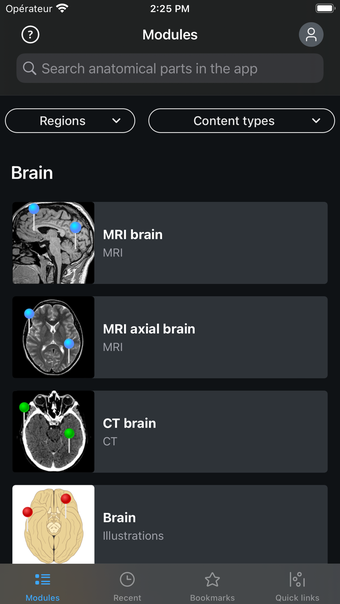

IMAIOS e-Anatomy es un atlas en línea de anatomía humana para médicos, enfermeras, estudiantes de medicina y técnicos en radiología. Utiliza IMAIOS e-Anatomy en tu smartphone o tablet para encontrar la ubicación de cualquier condición médica o estructura anatómica. El detallado e-Anatomy te proporcionará una referencia de acceso rápido de la anatomía humana y sus principales órganos y funciones.

Encuentra la ubicación de cualquier condición médica o estructura anatómica con IMAIOS e-Anatomy en tu smartphone o tablet. Busca enfermedades, anatomía y estructuras anatómicas, e incluso ve la ubicación de todos los puntos de referencia anatómicos. Puedes encontrar la ubicación de cualquier estructura o condición anatómica con la información médica detallada, fácilmente ingresando los detalles anatómicos relevantes.

Encuentra la ubicación de cualquier estructura o condición anatómica con IMAIOS e-Anatomy en tu smartphone o tablet. Utiliza la guía de anatomía para encontrar la ubicación de las estructuras anatómicas, enfermedades y trastornos, e incluso la anatomía y estructura de los dedos y manos.

IMAIOS e-Anatomy es un atlas médico. Utilízalo como referencia médica para averiguar dónde se encuentra cualquier condición médica o estructura anatómica en el cuerpo humano.

IMAIOS e-Anatomy es un atlas en línea de anatomía humana. Proporciona información médica detallada sobre la anatomía y estructura del cuerpo humano. Utiliza IMAIOS e-Anatomy en tu smartphone o tablet para encontrar la ubicación de cualquier estructura o condición anatómica.